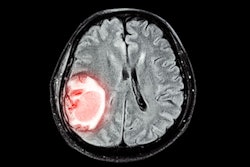

Many individuals with COVID-19-induced anosmia recover their sense of smell within a few months, the investigators explained. But a significant number continue to experience olfactory impairment. Dogahe and colleagues conducted a study that used MRS to assess metabolic patterns in patients' orbitofrontal cortex, seeking to identify any alterations within this brain region in those with the condition. (Proton MRS is an MR imaging method that characterizes a tissue's metabolic activity and biochemical composition by analyzing signals from hydrogen nuclei.)

Their research included 54 subjects categorized into two groups, each with 27 patients: one cohort with COVID-19-related anosmia and another cohort of patients who had COVID-19 but did not experience anosmia. The team used a tool called the Iran Recognition-Smell Identification Test (IR-SIT) over a three-month follow-up period to assess study participants' olfactory function and diagnose anosmia; all patients underwent proton MRS to identify changes of metabolites in the orbitofrontal cortex, including N-acetyl aspartate (NAA), choline (Cho), and creatine (Cr). It also investigated any correlation between the MRS data and the IR-SIT scores.